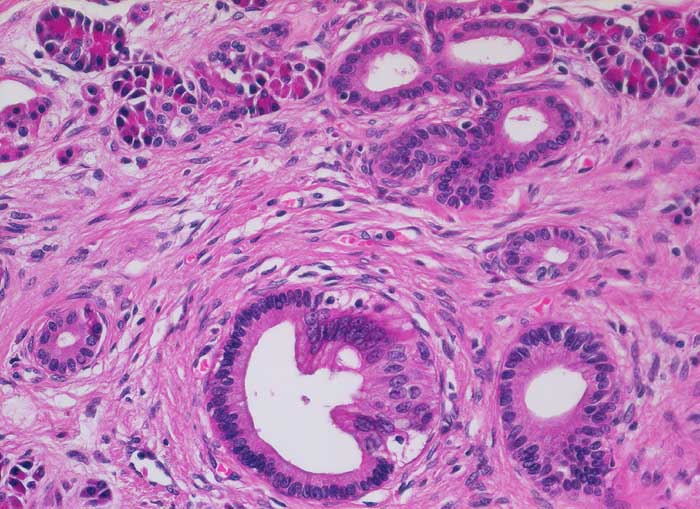

PathoPic – image database / PathoPic ID 5883 - Chronisch-sklerosierende Pankreatitis

Chronisch-sklerosierende Pankreatitis

Topographie

Beschreibung

Klinik

Alkoholiker mit rezidivierten akuten Pankreatitisschüben. Chronische Diarrhoe.

Histologie

Vergrösserung

200

Alter

49

männlich